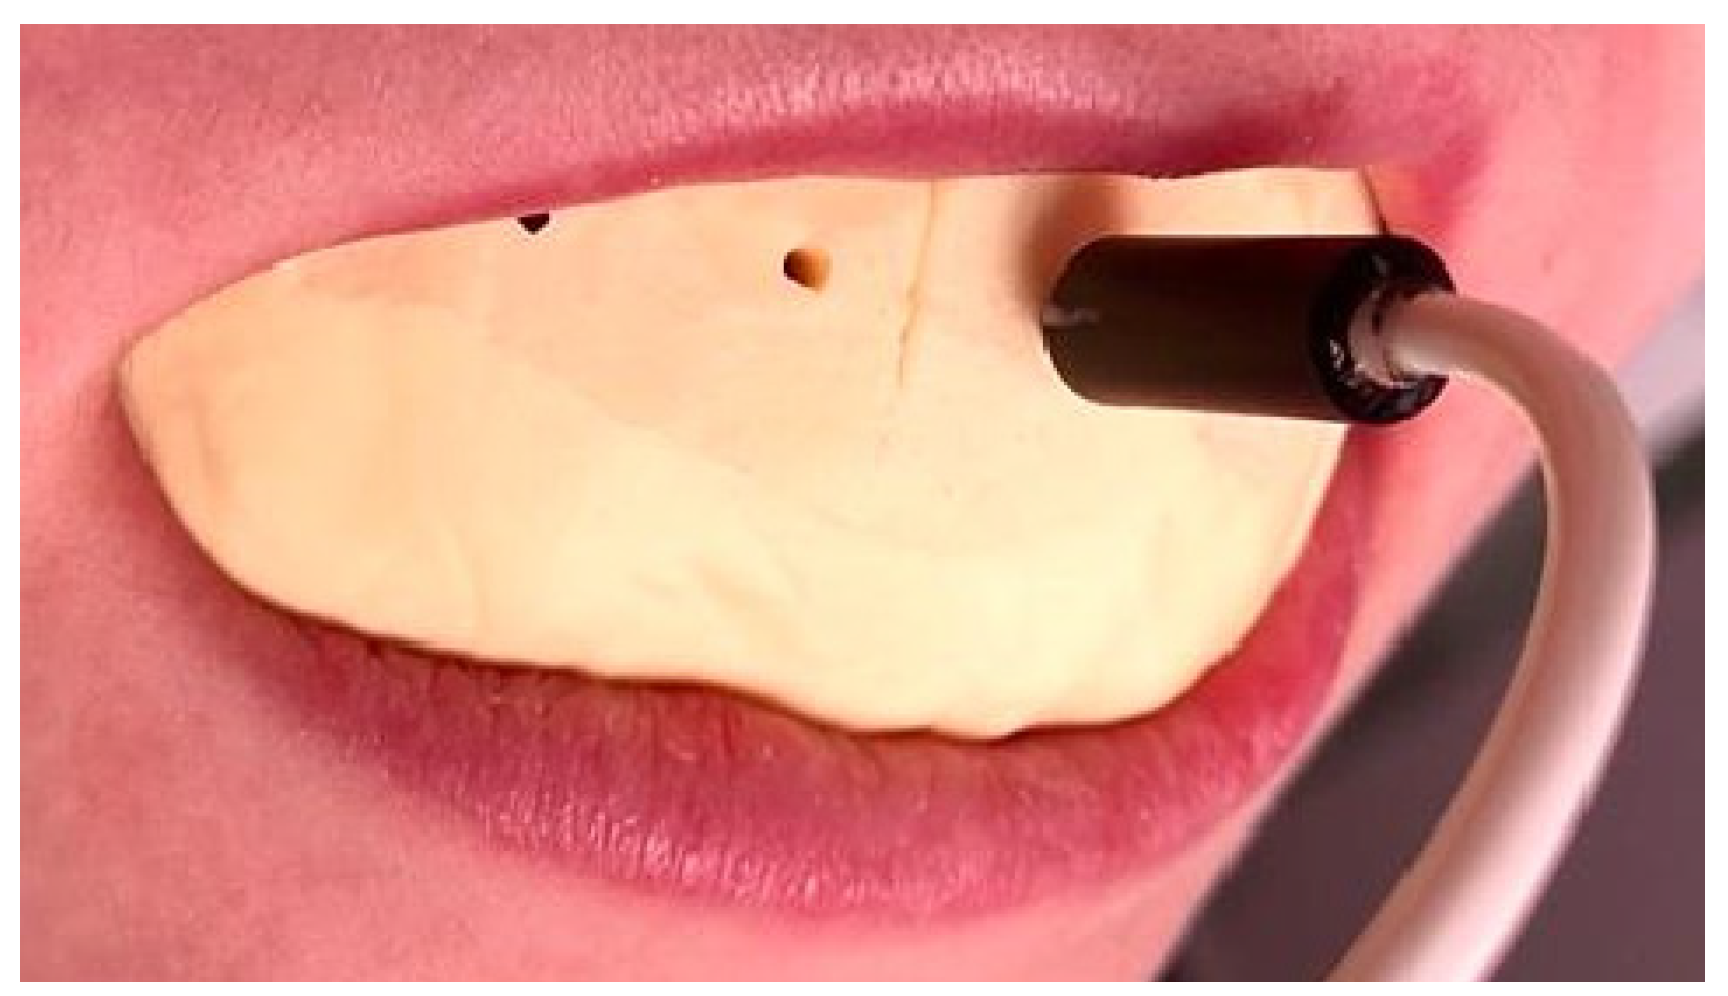

2.3. Debonding Systems

2.5. The Working Technique

2.6. Data Analysis